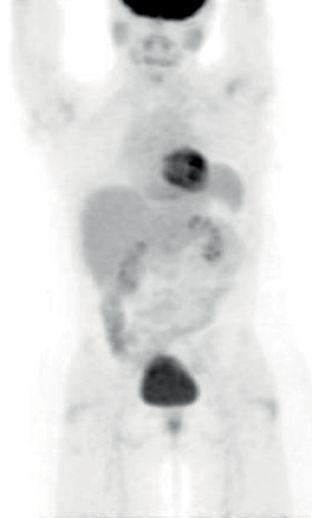

患者4:SQSTM1-NTRK1融合非小细胞肺癌的持久反应

45岁女性被诊断患有IV期NSCLC腺癌 , 肝脏和纵隔转移以及肥厚性骨关节病(HOA)症状 , 她曾接受过以前的铂类和培美曲塞治疗 。

基因检测发现 , NTRK融合基因 , 接受larotrectinib100 mg每日两次 , 出现快速反应 , 表现为第1周期(研究第8天)HOA症状 , 咳嗽和疲劳的改善以及第3周期完全没有咳嗽 。 第54天出现部分反应 。 反应持续时间> 12.88个月 。